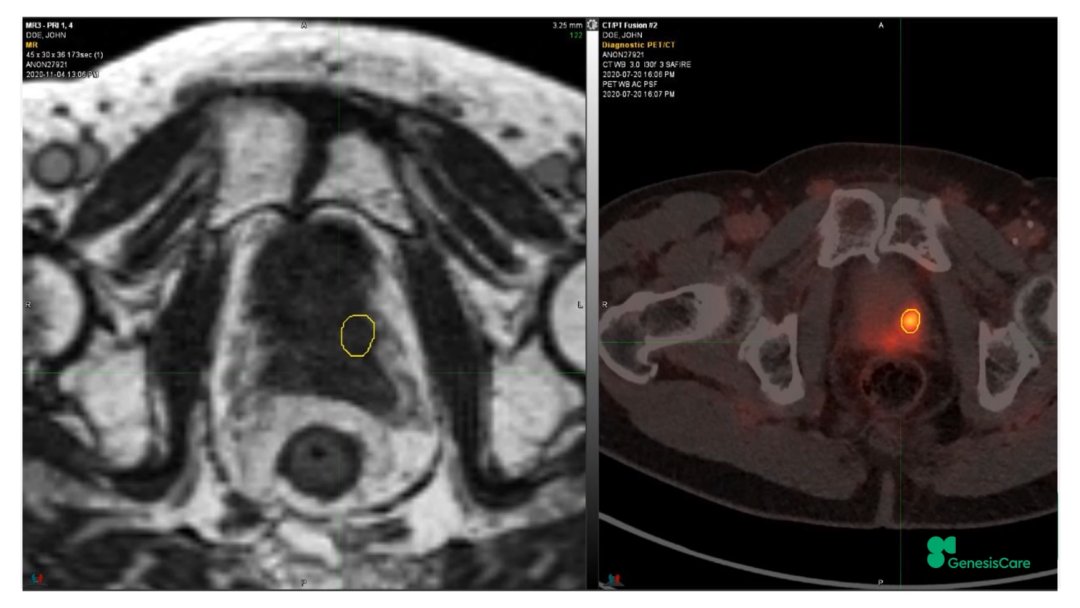

Dr. CamilleriÏÈÈÝÁËһλ72Ë꣬£¬£¬£¬£¬£¬£¬ÔÚ2006Äê½ÓÊÜÁË55Gy/20F·ÅÁƺ󸴷¢µÄǰÏßÏÙ°©»¼Õß¡£¡£¡£¡£¡£¡£ÆäʱËüµÄPSAΪ28£¬£¬£¬£¬£¬£¬£¬¾Ö²¿ÍíÆÚ£¬£¬£¬£¬£¬£¬£¬ÆÚ±ðΪT3aN0M0¡£¡£¡£¡£¡£¡£PET-CTÏÔʾǰÏßÏÙ×óºó²¿¾Ö²¿¸ß´úл£¬£¬£¬£¬£¬£¬£¬»î¼ìҲ֤ʵÁËÕâÒ»µã£¬£¬£¬£¬£¬£¬£¬²¢ÇÒ»î¼ìЧ¹ûÅú×¢Ö×ÁöÇÖÈë×ó²à¾«ÄÒÏٵײ¿¡£¡£¡£¡£¡£¡£½«ÆäMRIdian MRIͼÏñºÍPET-CTͼÏñÈںϺ󣬣¬£¬£¬£¬£¬£¬ÔÙÆ¾Ö¤»î¼ìЧ¹ûÈ·¶¨°ÐÇø£¬£¬£¬£¬£¬£¬£¬¼ûFigure 20-22£¬£¬£¬£¬£¬£¬£¬²¢ÖÆ×÷·ÅÁÆÍýÏë¡£¡£¡£¡£¡£¡£·ÅÁƼÁÁ¿Îª35Gy/5´Î£¬£¬£¬£¬£¬£¬£¬Äý½º×è¸ôÎïºÜºÃµØ°üÀ¨ÁËÖ±³¦£¬£¬£¬£¬£¬£¬£¬¼ûFigure 23£¬£¬£¬£¬£¬£¬£¬°ÐÇøºÍΣ¼°Æ÷¹ÙÊÜÁ¿¼ûFigure 24¡£¡£¡£¡£¡£¡£»£»£»£»£»£»£»¼ÕßÓÚ2020Äê12Ô½ÓÊÜÖÎÁÆ£¬£¬£¬£¬£¬£¬£¬ËûÌåÖʺܺ㬣¬£¬£¬£¬£¬£¬ÔÚ·ÅÁÆÊ±´úºÍÖ®ºó£¬£¬£¬£¬£¬£¬£¬¼á³ÖÿÖÜÈý´Î5¹«ÀïÅܲ½£¬£¬£¬£¬£¬£¬£¬Ê¼ÖÕδ·ºÆðGUºÍGI¶¾ÐÔ¡£¡£¡£¡£¡£¡£ËûµÄPSA×îµÍֵΪ0.45£¬£¬£¬£¬£¬£¬£¬ÔÚ2022Äê5ÔµÄËæ·ÃÊý¾ÝÖУ¬£¬£¬£¬£¬£¬£¬ØºÍè¼¤ËØË®Æ½»Øµ½ÁËÕý³£µÄ33%¡£¡£¡£¡£¡£¡£ÔÚ2022Äê1ÔµķÅÁƺóPSMA PETµÄͼÏñÉÏ£¬£¬£¬£¬£¬£¬£¬Î´¼ûÖ×Áö¸ß´úл¼ûFigure 25¡£¡£¡£¡£¡£¡£